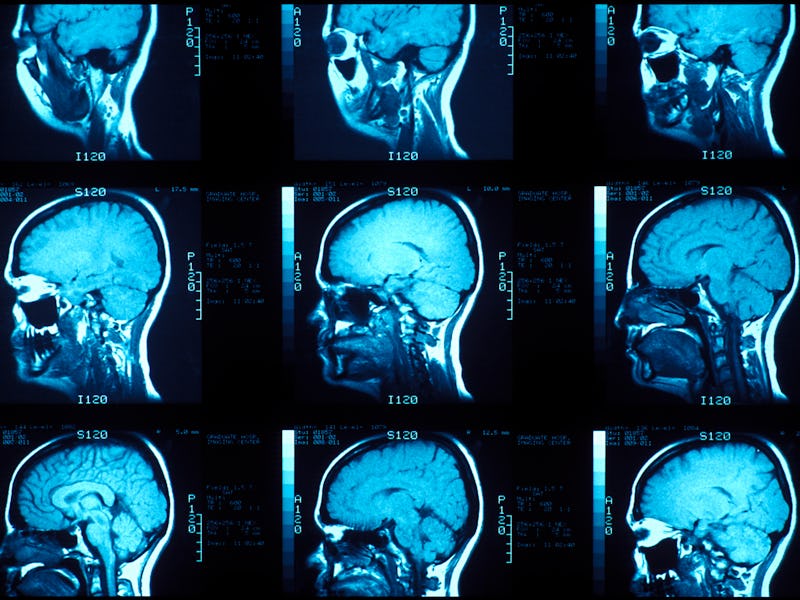

Using a sample of brain scans from the UK Biobank, a large-scale biomedical database, scientists at McGill University found loneliness was linked to three changes in the brain:

- Higher grey volume in areas of the brain involved in that network.

- Greater connectivity in the default mode network

- Heartier structure in a bundle of nerve fibers called the fornix, which carries signals from the hippocampus to that network

Yellow areas of the brain had higher grey matter volume in lonely people, green areas showed lower grey matter volume. But overall, lonely people had more grey matter volume in the areas of the default mode network.

This study examined brain scans taken from 38,701 people in the UK Biobank database. Thirtneen percent of people in the sample analyzed reported they felt lonely, according to surveys given to participants as part of the BioBank project.